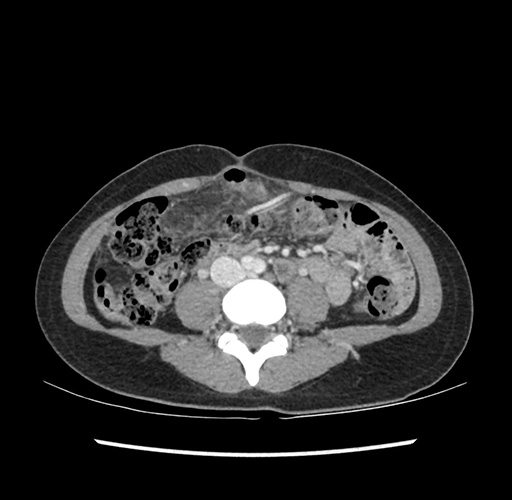

Imaging Analysis

Look through the patient's CT scan to identify any areas of concern for the necessary procedure.

Based on your CT findings, which issue(s) would give reason for "planned slowing down moment(s)" in this case?